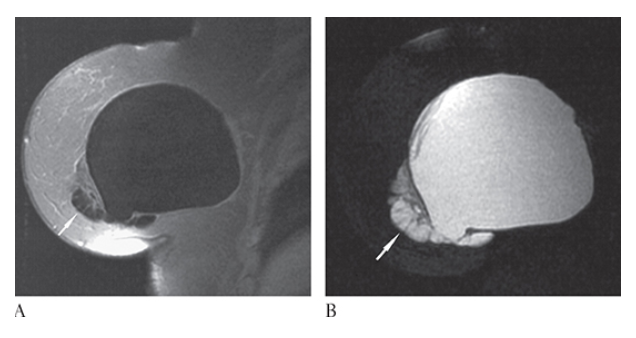

What is A

Rupture of Breast Implant. T1-weighted and T2-weighted

What is B

Rupture of Breast Implant. T1-weighted MR images of the breast show collections of silicone (arrows) outside the implant lumen that are diagnostic of extracapsular rupture.